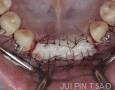

Baseline

Surgery